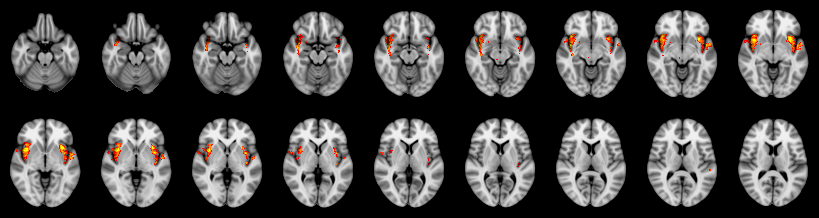

Pain study, Voxel-level, Corrected

Combined

Tippett:

Fisher:

Stouffer:

Edgington:

Mudholkar–George: